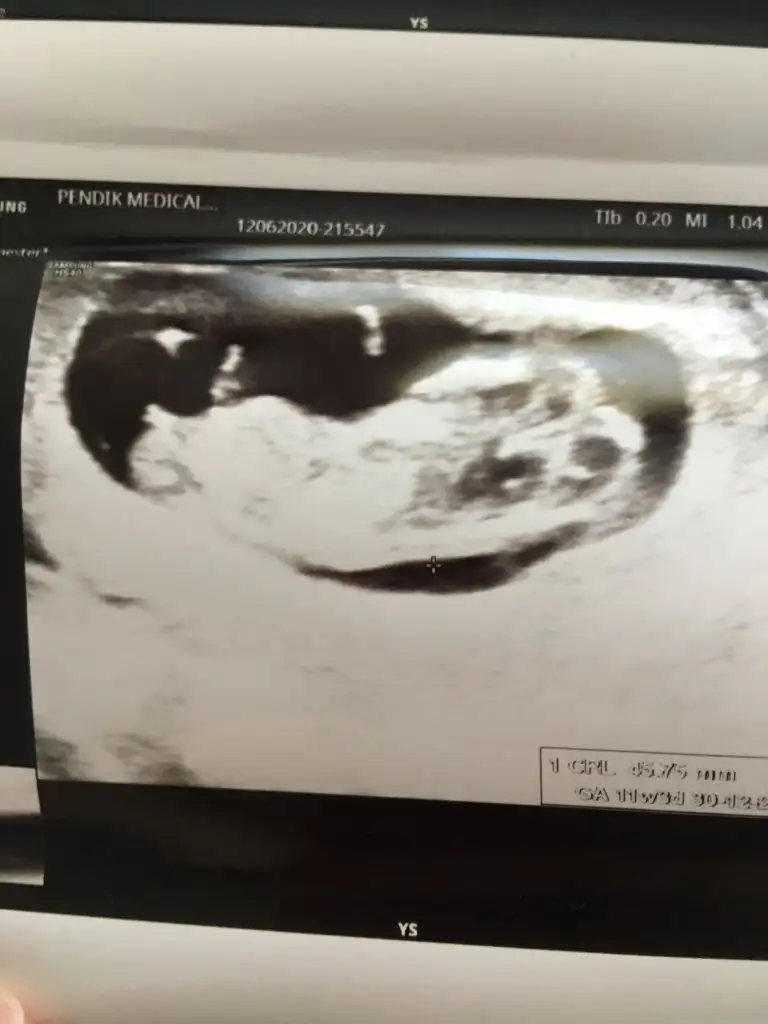

I ikra -meyra bende yorumunuzu merak ediyorum 10 haftalik tam

Eklentiler

• 1593428018684230887551.webp

1593428018684230887551.webp

51,5 KB · Görüntüleme: 74

Merhabalar herkese sağlıklı doğumlar ve bebişler dilerim. benim bebeğim için de bir tahmininiz var mıdır? :)

• IMG_20200630_142810.webp

IMG_20200630_142810.webp

14,3 KB · Görüntüleme: 84